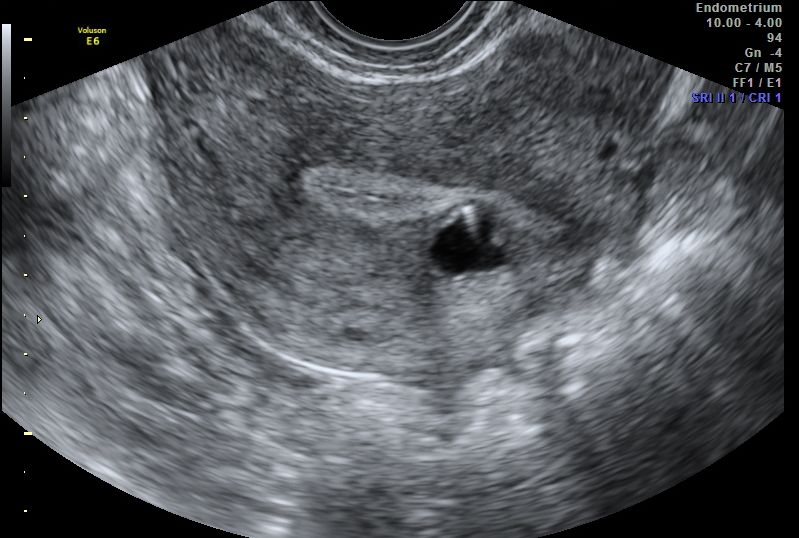

Luis Alonso Pacheco. Centro Gutenberg. Málaga. Spain INTRODUCTION Adenomyosis is defined as the presence of ectopic endometrial tissue inside theContinue Reading